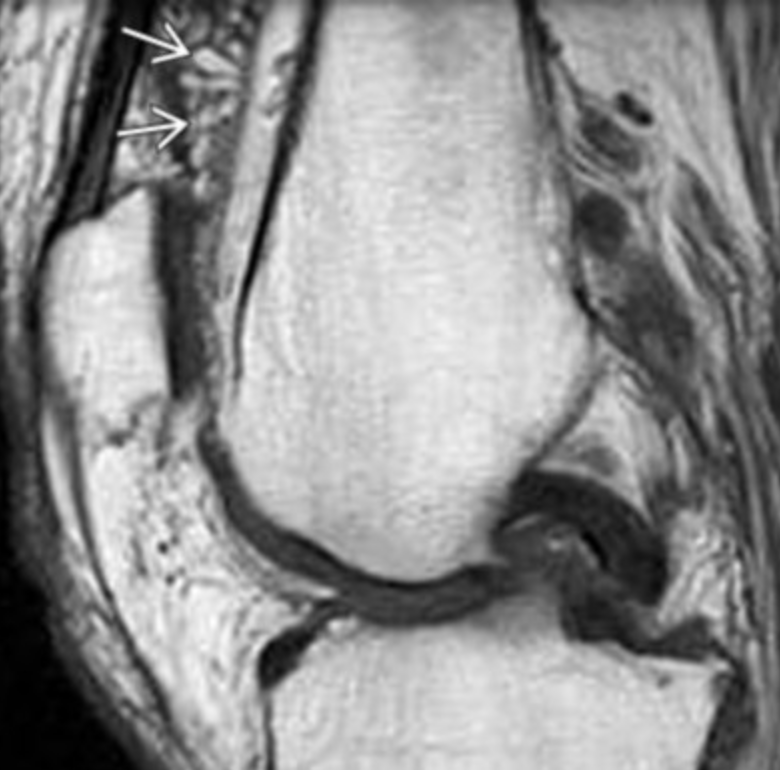

Pigmented Villonodular Synovitis (PVNS)

• Monoarticular (70% in knee, 10% hip)

• Synovial proliferation

• Large subchondral cysts